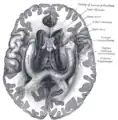

![]() Base of brain (Tuber cinerum visible at center). | |